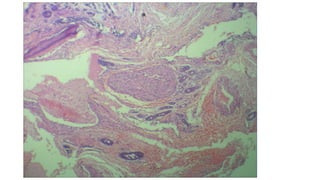

Section studied from R nasal mass shows tumor composed of tumor

cells arranged predominantly in cribriform and tubular pattern

tumor cells are small, round to oval with scanty cytoplasm,

hyperchromatic nuclei and indistinct cell border

pseudocyst formed by the tumor cells are filled with eosinophilic

hyaline material.

tumor cells are seen infiltrating the adjacent mucosal glands and

interstitium.

Neural invasion is seen

adjacent attached respiratory epithelium show normal histology

• Microscopic examination: Sectionstudied from R nasal mass shows tumor composed of tumor cells arranged predominantly in cribriform and tubular pattern tumor cells are small, round to oval with scanty cytoplasm, hyperchromatic nuclei and indistinct cell border pseudocyst formed by the tumor cells are filled with eosinophilic hyaline material. tumor cells are seen infiltrating the adjacent mucosal glands and interstitium. Neural invasion is seen adjacent attached respiratory epithelium show normal histology

• Impression: Adenoid cysticcarcinoma with perineural invasion